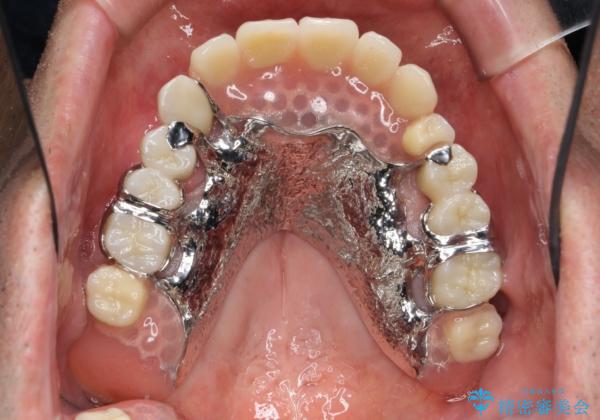

- 残った前歯のほとんどがグラグラし食事ができず、我慢の限界に達し治療を希望され来院されました。

今後しっかりとした食事を楽しめるような咬合機能を回復するために、奥歯はインプラントによる咬合機能回復を行い、前歯は入れ歯で審美性・機能性を回復していきます。

- 250万円(ストローマンインプラント×5・骨造成・チタンカスタムアバットメント×5・ジルコニアクラウン×7・金属床部分床義歯)費用は治療当時の料金となります

奥歯は取り外しの必要のないインプラント補綴を行うことでしっかりと食事を行うことができます。

また前歯の部分床義歯も奥歯部分のインプラント支台クラウンで支えることによりずれたりはずれたりすることなくしっかりと噛むことができます。

![[インプラントオーバーデンチャー] インプラントで奥歯を支える部分床義歯の治療中](https://seimitsushinbi.jp/wp/wp-content/uploads/2020/05/b8ced9b39b77f4185682a17840c92188-500x350.jpg?v=1590579818)